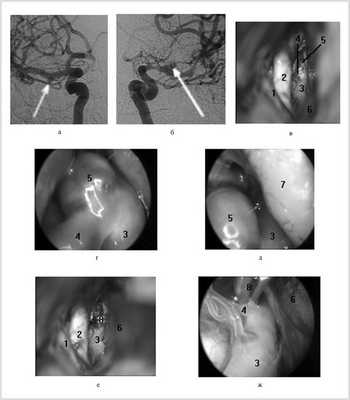

Клипирование аневризмы СМА из контралатерального доступа выполнено у одного больного с множественными «зеркальными» аневризмами обеих СМА (рис. 5). После клипирования разорвавшейся аневризмы правой СМА выполнен контралатеральный транссильвиевый доступ к аневризме левой СМА. Выделенная аневризма была милиарного размера и имела широкую шейку, распространяющуюся на крупную височную ветвь СМА. При помощи ВЭСА удалось осмотреть аневризму под большим увеличением, исключить связь ее тела с перфорирующими ветвями и после клипирования убедиться в проходимости височной ветви СМА. В данном наблюдении контралатеральный подход к АА СМА позволил избежать трепанации черепа с противоположной стороны и, фактически, второй операции.

Рис. 5. Клипирование аневризмы контралатеральной средней мозговой артерии с использованием видеоэндоскопической ассистенции у больного П., 33 года, на 24-е сутки после субарахноидального кровоизлияния. а, б — право- и левосторонняя каротидные ангиограммы: аневризмы М1-сегментов правой и левой средних мозговых артерий (обозначены стрелками); в — вид структур контралатеральной сильвиевой щели через микроскоп; г, д — вид через эндоскоп с тубусом 0°: аневризма средней мозговой артерии в области устья темпорополярной ветви; е — вид через микроскоп: аневризма клипирована; ж — вид через эндоскоп с тубусом 30°. Клипса точно расположена на шейке аневризмы, темпорополярная ветвь средней мозговой артерии не компримирована. 1 — левый зрительный нерв, 2 — правый (контралатеральный) зрительный нерв, 3 — правая средняя мозговая артерия (контралатеральная), височная ветвь правой средней мозговой артерии, 5 — аневризма правой средней мозговой артерии, 6 — шпатель на базальной поверхности правой лобной доли мозга, 7 — правая лобная доля мозга, 8 — клипса на шейке аневризмы.